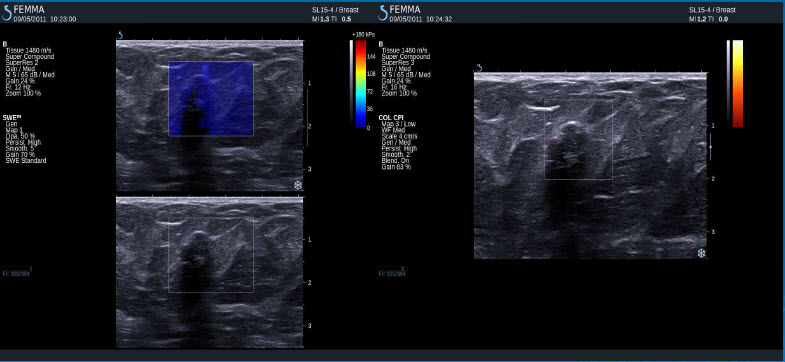

Pozitivní výsledky elastografie / histologicky potvrzená benignita

Intraduktální papilom

Fibroza

Fibrocystické změny, mírně floridní duktální hyperplasie, ložisko cikatrizace

Fibrozní změny, duktální hyperplazie

Floridní duktální hyperplasie a apokrinní metaplasie